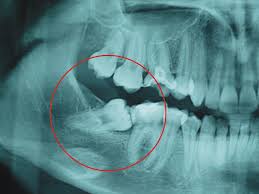

Wisdom tooth surgery de $4200 a $2900

*** Xray not includen $350 MXN